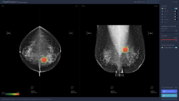

루닛, 유방암 진단 소프트웨어 공개...정확도 97%

의료 인공지능 기업 루닛은 유방촬영술을 위한 인공지능 소프트웨어 루닛 인사이트(Lunit INSIGHT for Mammography)를 공개했다. 루닛 인사이트는 97%의 정확도로 유방암을 발견하는 의료 인공지능 소프트웨어로 촬영된 영상 이미지를 업로드하면 종양의 위치는 히트맵으로, 종양의 악성 정도는 점수로 즉각 표기된다.

루닛은 임상 연구 결과 루닛 인사이트가 영상의학과 전문의의 판독 성능에…